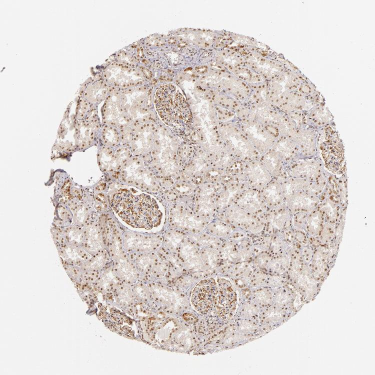

BioDASH is currently being expanded to handle gene expression data, merged with clinical, histological, and toxicity findings, all linked through RDF-OWL:

Gene expression data from malignant and normal tissues based on GeneLogic's GeneExpress database were obtained from the work of Liu et al., 2003. The expression table files were converted into RDF using an Excel script.